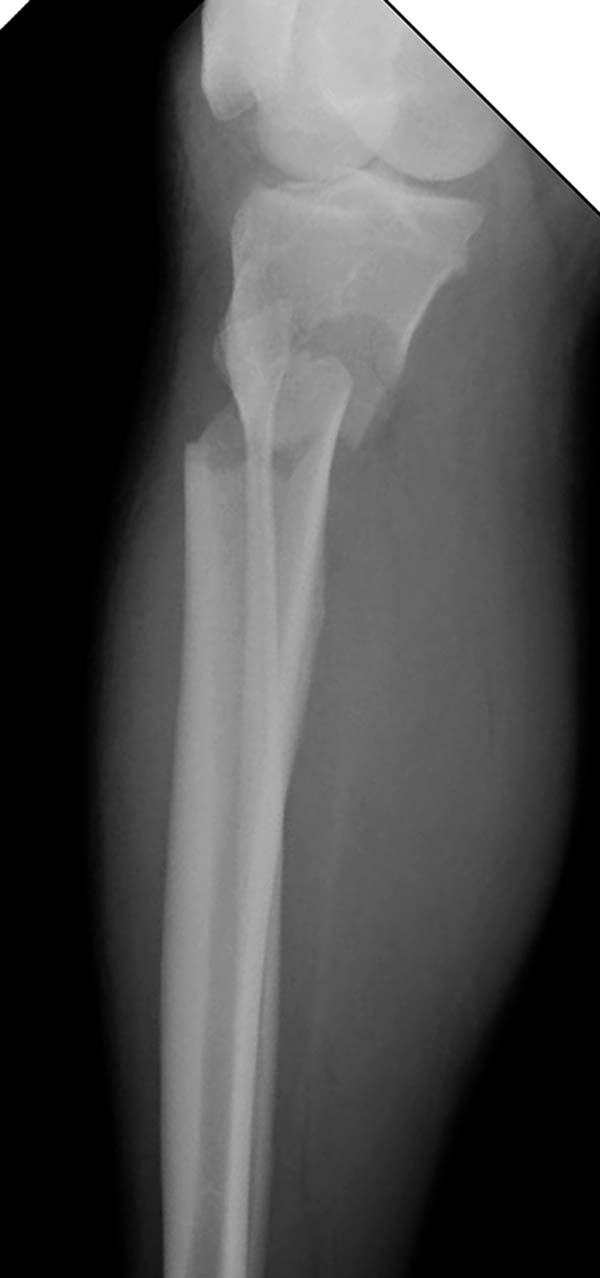

Здесь, кроме перелома верхней трети голени, имеется вовлечение сустава, и, чтобы не пропустить смещение суставной поверхности, надо делать КТ. Срезы КТ покажут о необходимости субхондральной фиксации, которая проводится 3.5 мм параллельными шурупами (Raft technique). Не имеет значения, как проводить: отдельно субхондрально или через верхний ряд пластины. Главная задача фиксации удержать суставную поверхность от коллапса в вальгус или варус.

Здесь случай, так называемого floating knee перелома выше и ниже коленного сустава.

Имя     : 1 Proximal tibia injury.JPG